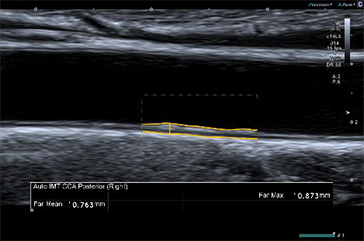

超音波検査にかかる時間は計測項目の量に応じて増加する。必要な検査項目を出来るだけ短時間で行えるように,一部のアプリケーションには深層学習や機械学習といったAI(注1)を用いている。例えばAuto IMTでは,総頸動脈の内中膜複合体厚(Intima Media Thickness.IMT)を任意の領域において,従来(注2)よりも短時間で自動トレースすることが可能となった。

AI技術を使って開発されたアルゴリズムによって得られたトレースラインで計測されたAuto IMT